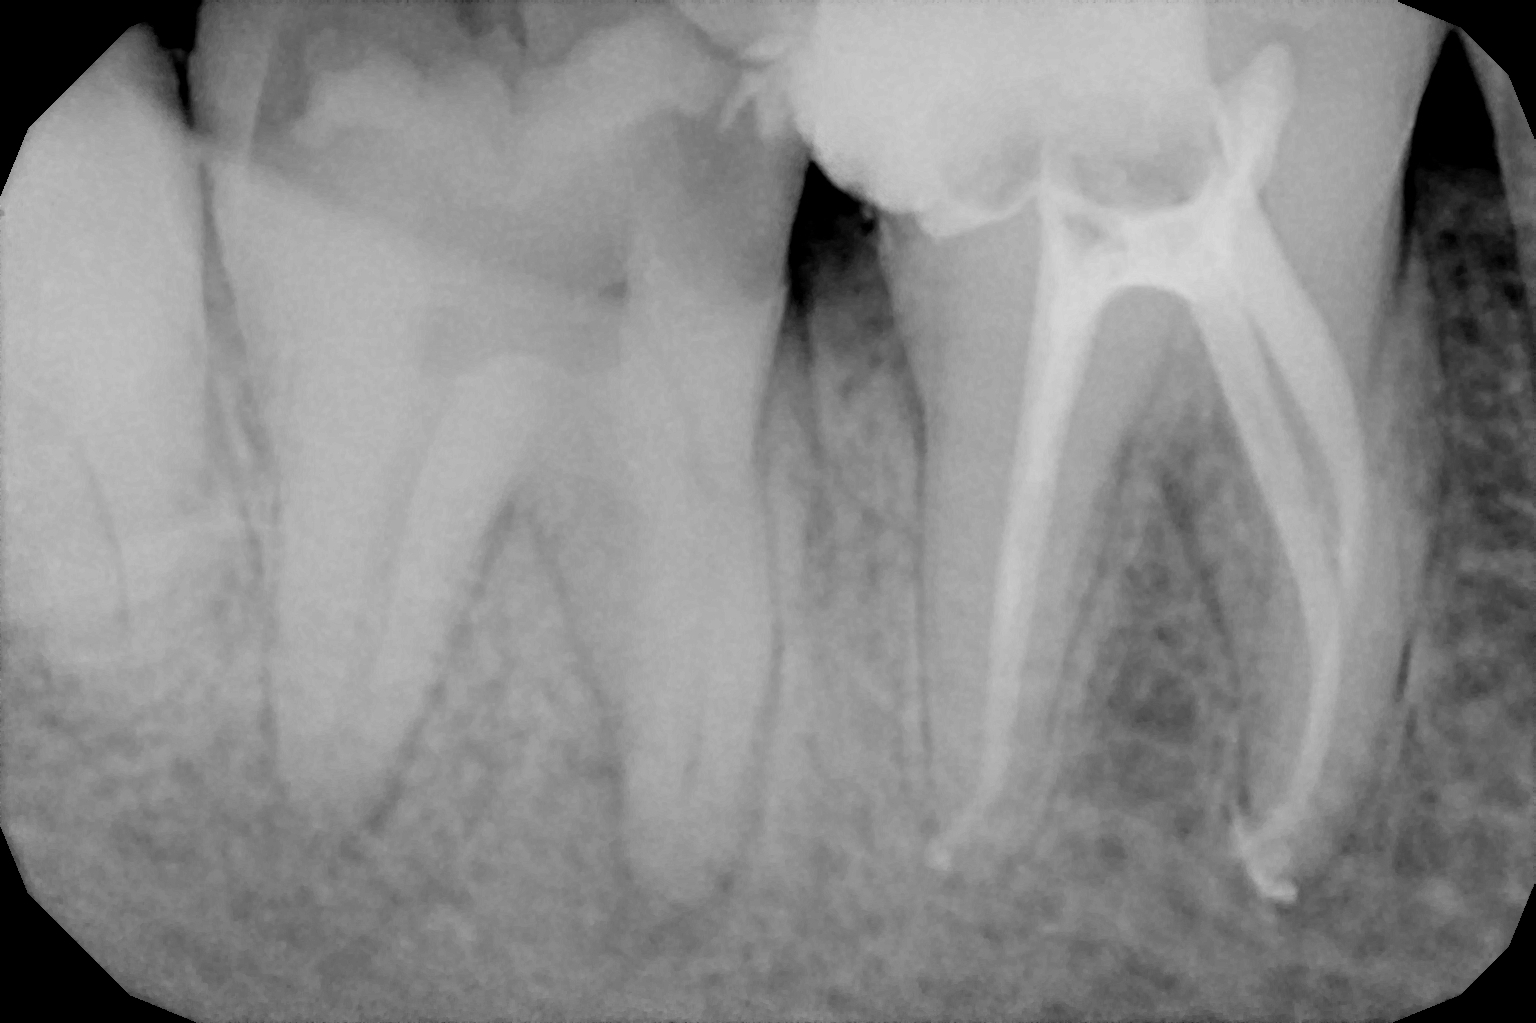

When the tooth is is sensitive to particularly hot and cold. When you cannot chew from that side or there is associated action of pain and swelling with same tooth, root canal treatment can save the tooth. For root canal treatment our clinic is equipped with state-of-the-art facility. We are following the protocol that is universally accepted and considered as a gold standard We are using rubber Dam for maximum possible cases. The root canal treatment is done under local anaesthesia that's why mostly it is painless . The rubber Dam isolation helps in proper irrigation and it provides much needed ease to the operating dental surgeon and the patient . The sealer and filling material are one of the Prime requisite of quality root canal treatment, it needs use of multiple X rays to really judge whether the results are acceptable or not. In older days root canal was just about cleaning the decade portion, removing the Pulp and filling it with biocompatible material but nowadays the root canal treatment it is very much advanced the precision is increased manifold. The materials and armamentarium that is required for efficient root canal have advanced in exclusion initial ways the the Abstract of all these things is the patients are getting great results after root canal treatment. Only the root canal is not sufficient to make a tooth functional again ,it needs use of Core buildup material and complete coverage Crowns according to the tooth position. During Covid19 time we have studied and implemented use of of high strength composites in our practice and the results of it are amazing many times it has saved tooth from being restored with crown. In some cases where the tooth is grossly carious we need a complete coverage crown. The materials and the Crown materials are are available in various price ranges. We prefer only the best of materials for our patients. We believe that to perform best treatment we need best of the armamentarium and best of the material for our patients who value and deserve the best of the treatment.